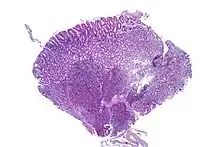

| Stomach biopsy with pancreatic heterotopia in the submucosa. H&E Stain. | |

| Diagnostic method | Biopsy, histologic evaluation |

An ectopic pancreas is an anatomical abnormality in which pancreatic tissue has grown outside its normal location and without vascular or other anatomical connections to the pancreas.[2] It is a disease which is congenital[2] and is also known as heterotopic, accessory, or aberrant pancreas.[3]

The diagnosis of ectopic pancreas can be challenging. Confirmation of the diagnosis requires tissue sampling, via biopsy or surgical resection.